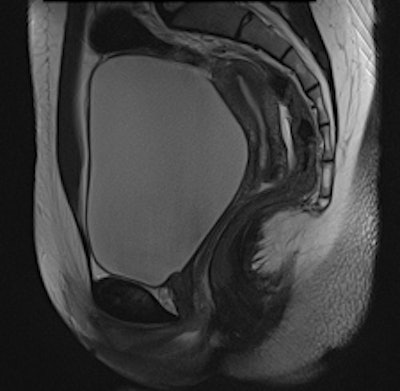

The uterine zonal anatomy and cervix are more sharply delineated on the BLADE image (right); however, SNR and CNR are higher on the conventional T2-weighted image (left). All images courtesy of Dr. Bianka Freiwald-Chilla.Previous studies have focused primarily on visual and qualitative assessment of images, so Froehlich and colleagues prospectively compared overall image quality, contrast, and diagnostic information of the recently implemented T2-weighted BLADE TSE sequence with the conventional Cartesian T2-weighted TSE sequence in female pelvic organs.

They found BLADE significantly (p < 0.0001) reduced motion and ghosting artifacts and showed improved conspicuity, but overall image quality did not differ significantly in the 47 patients who underwent sagittal BLADE and conventional TSE at 1.5-tesla after glucagon administration. In the majority of cases (53.2% versus 59.6%), radiologists preferred conventional TSE due to better image contrast and visibility of free pelvic fluid. Signal-to-noise ratio (SNR) and contrast-to-noise ratio (CNR) were significantly higher on conventional TSE.

Cervical carcinoma: The uterine zonal anatomy and bladder wall as well as the bowel loops are more sharply delineated on the BLADE image (right); however, SNR and CNR are higher on the conventional T2-weighted image (left)."Indeed, conventional T2-weighted TSE provided a significantly better visibility of free pelvic fluid or cystic structures (i.e., a relatively higher effective T2 weighting) in numerous cases," the researchers noted.